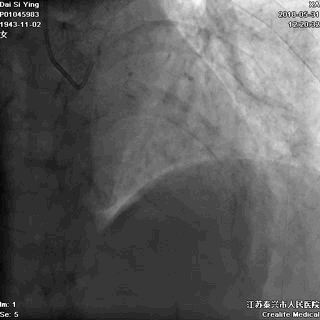

我们曾接诊过一个姓戴的老奶奶,79岁,她出现胸痛后,先是自己在家观察和处理,过了9小时还没缓解,才赶往医院。我们马上进行了急诊手术,很成功,命是保住了,但因为太迟来就诊,心脏功能已经严重受损。

术后,她反复出现心衰,生活质量明显下降。

血管闭塞

血管开通

记住:时间就是心肌,时间就是生命。每耽误一分钟,就意味着更多心肌细胞坏死。